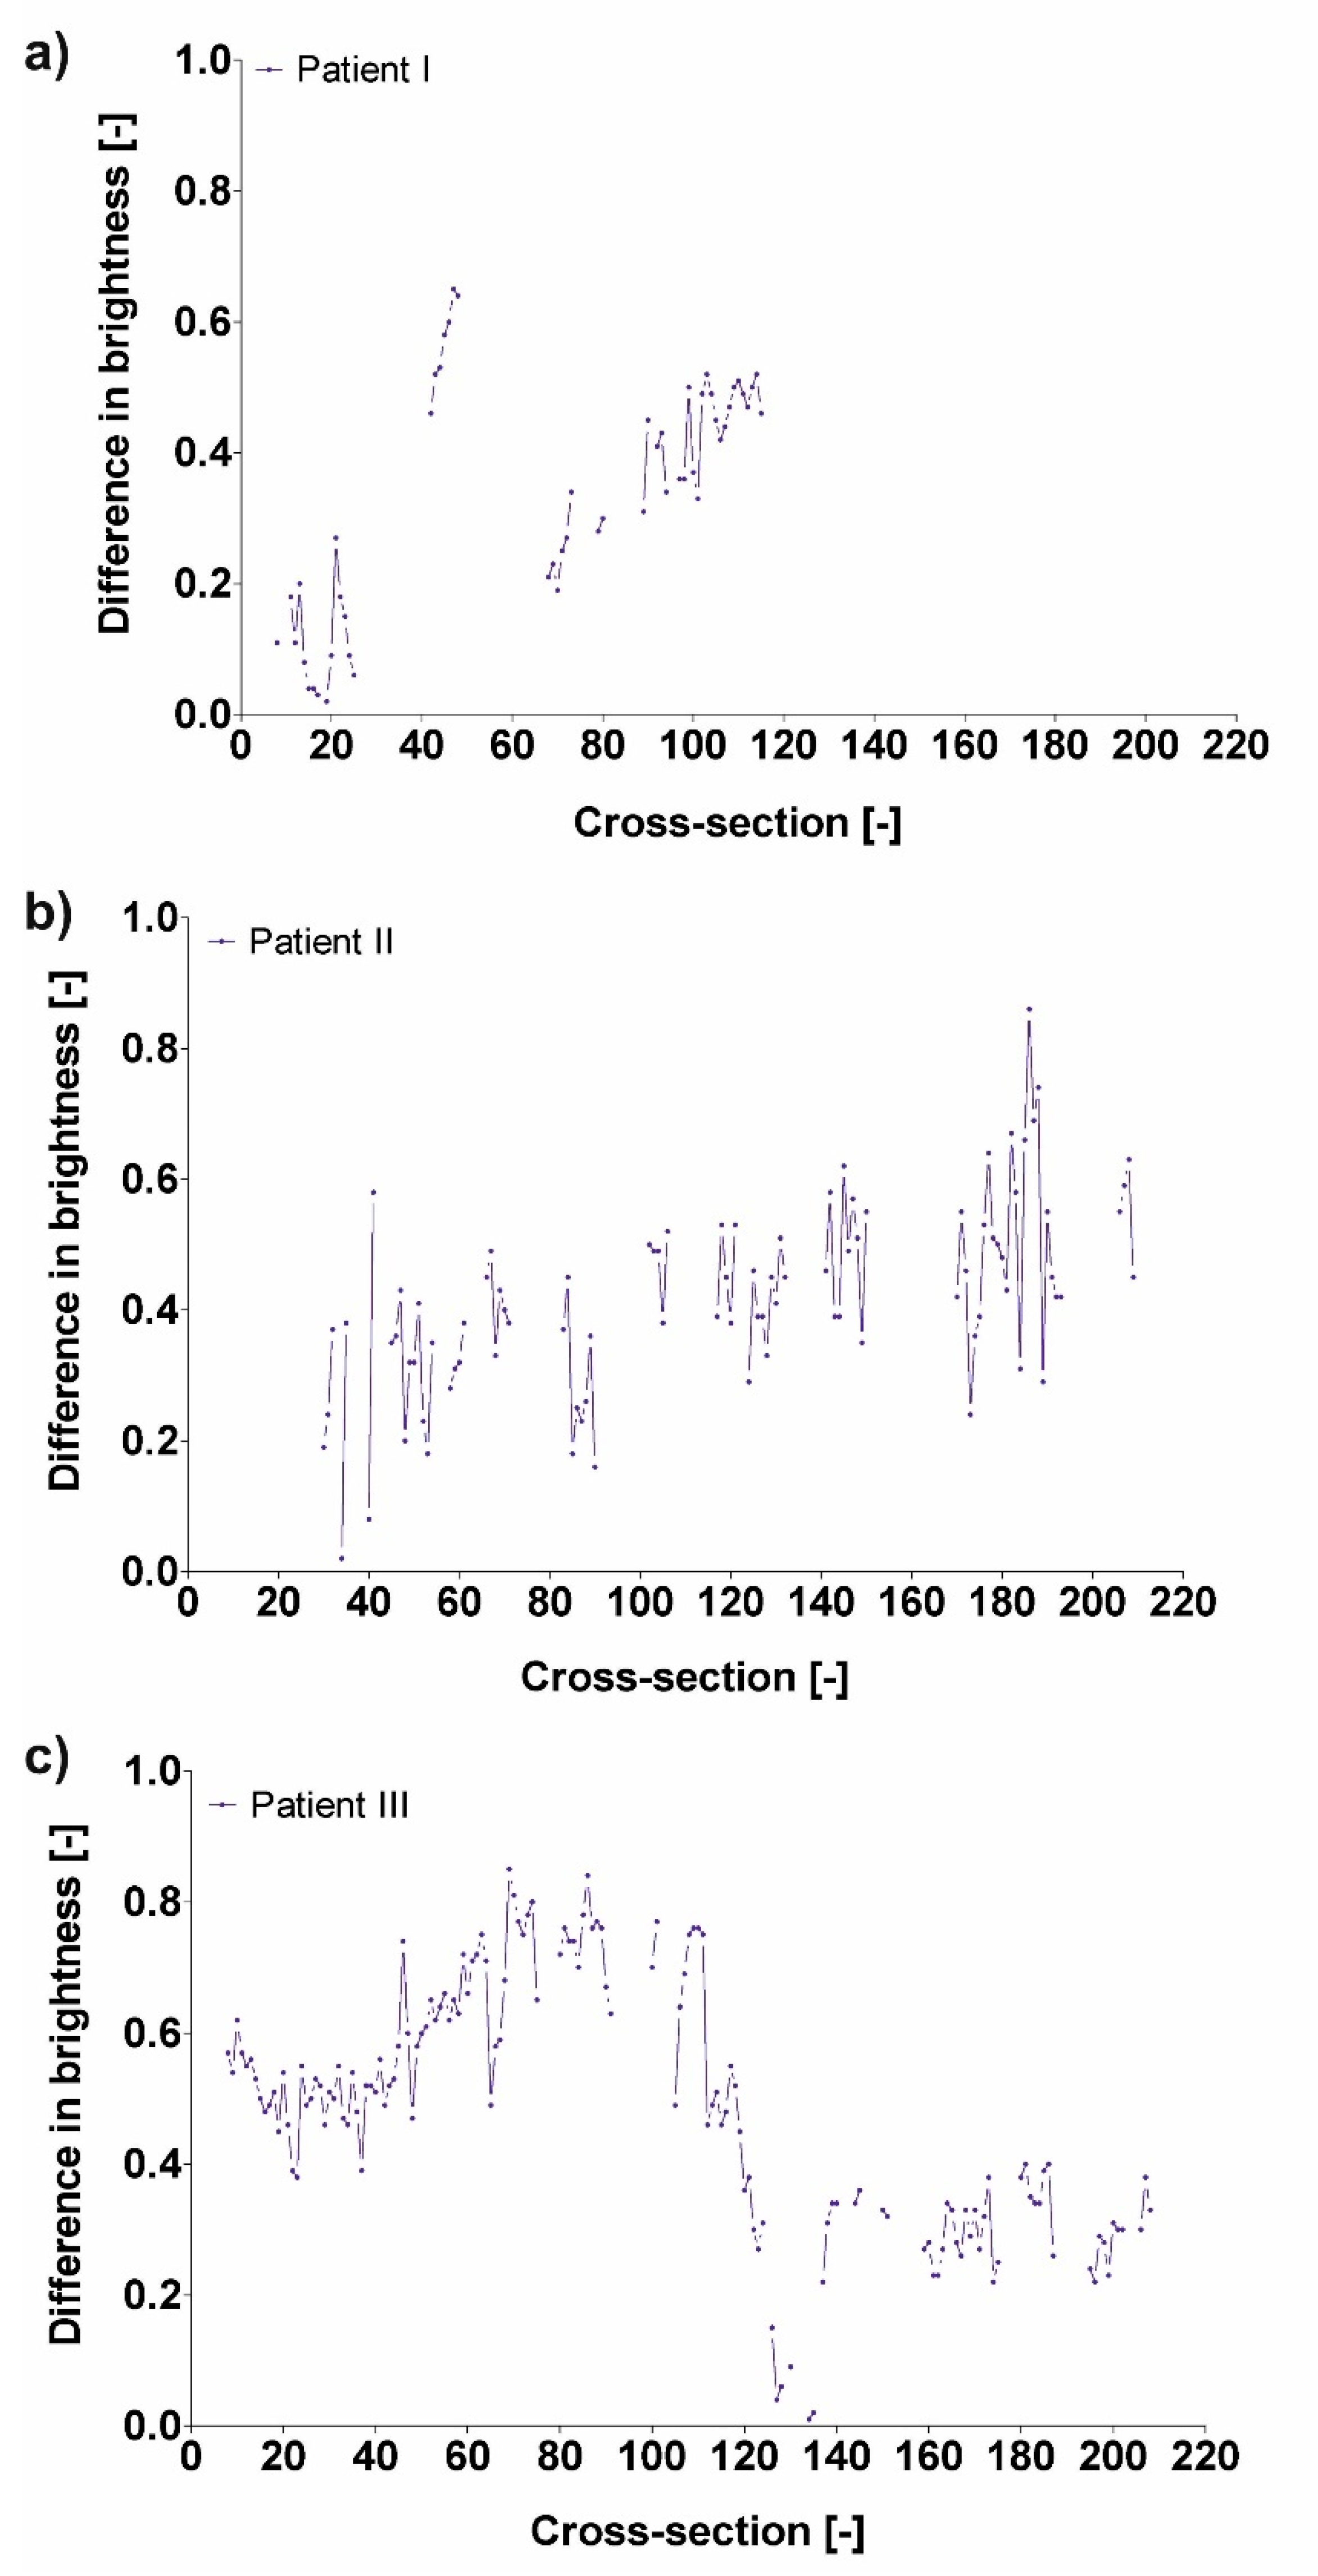

3.3. Difference in Brightness Value and Diameter

| Patient | Difference in Brightness |

|---|---|

| Pat I | 0.33 ± 0.18 |

| Pat II | 0.42 ± 0.14 |

| Pat III | 0.48 ± 0.20 |